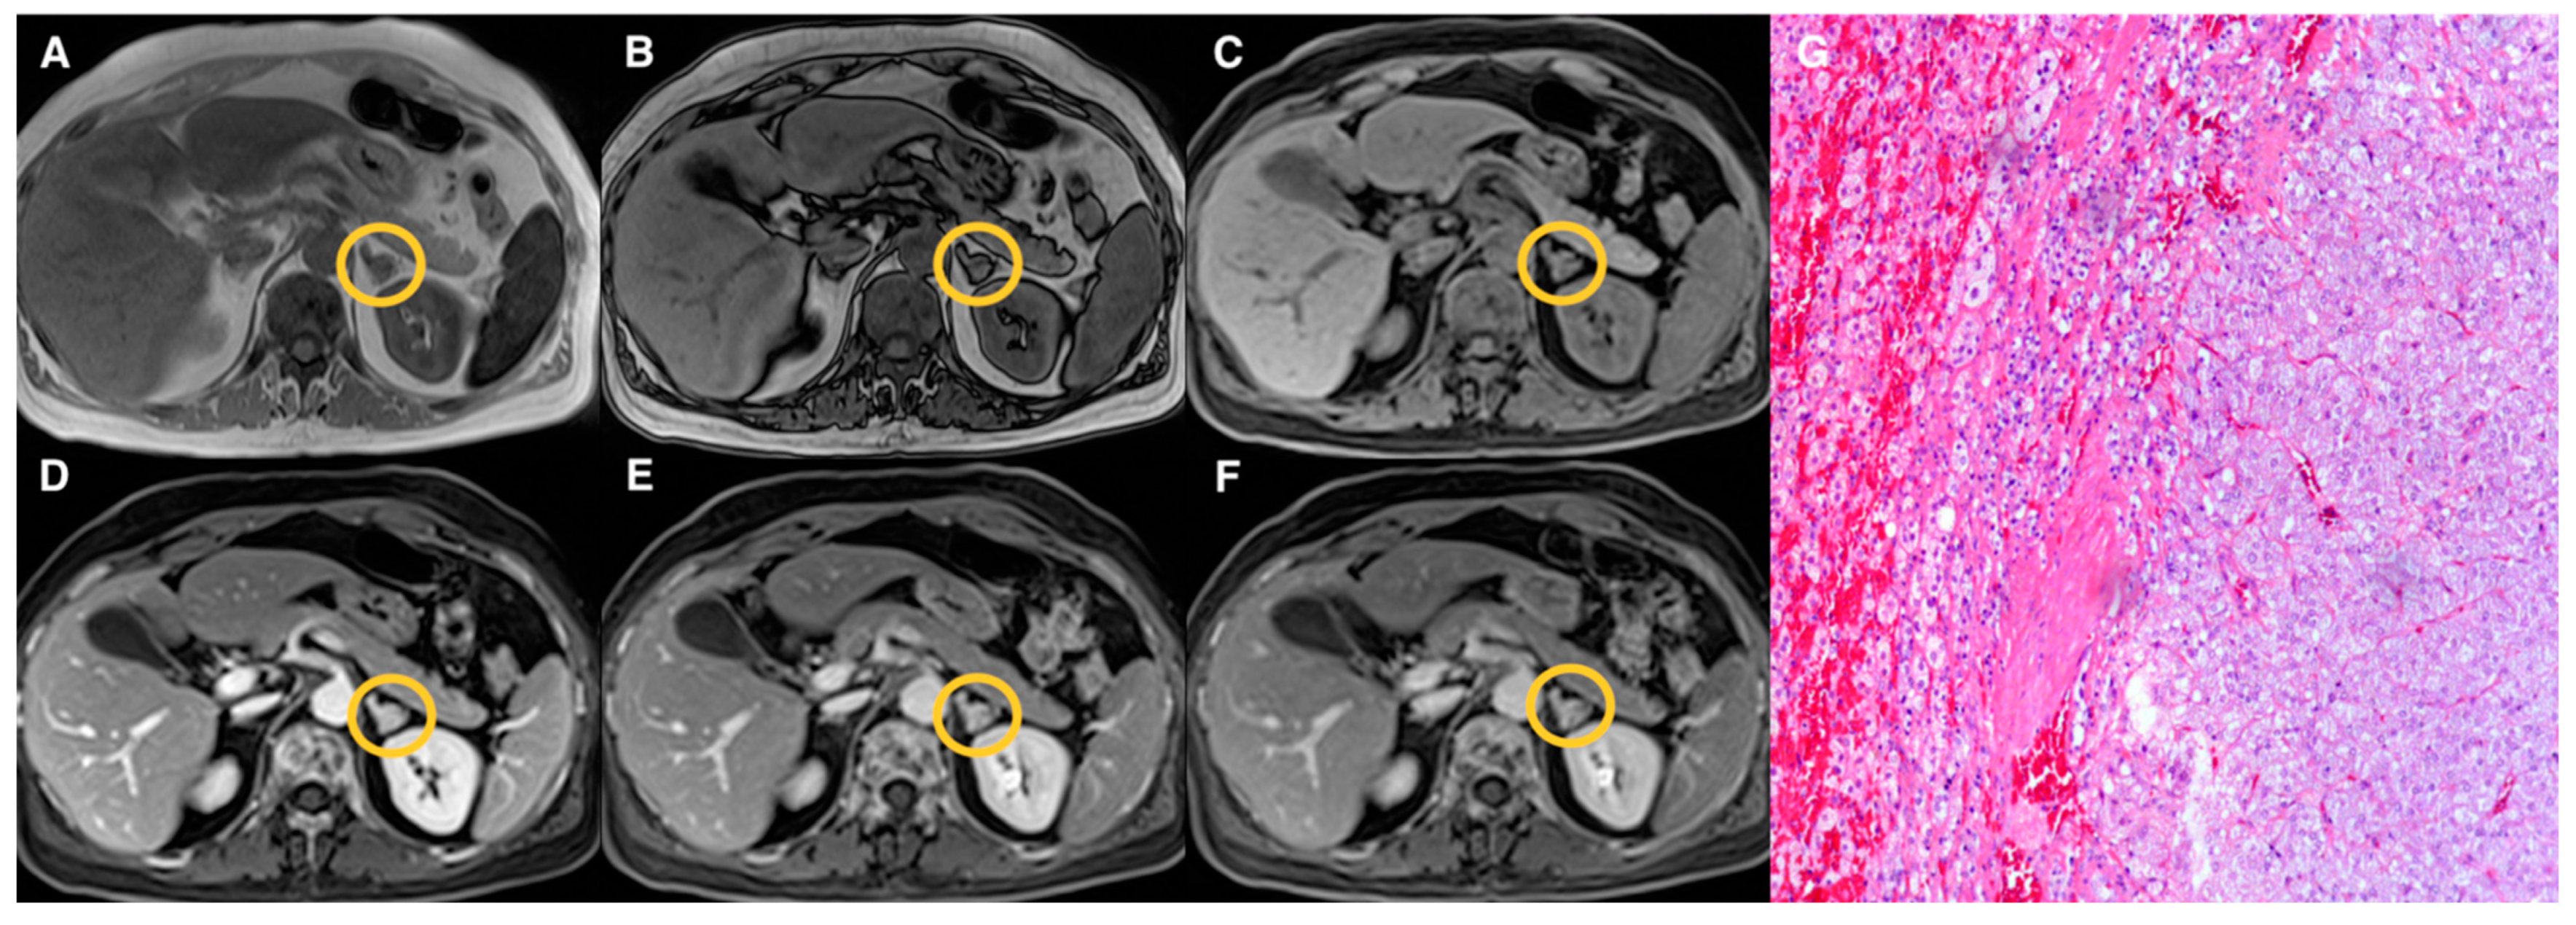

| Groups | Qualitative CS Signal Drop | Lesion Type | Total |

|---|---|---|---|

| 1 | Homogeneous | Adenomas (n = 19) | 19 |

| 2 | Heterogeneous | Adenomas (n = 17) Pheochromocytomas (n = 3) Myelolipomas (n = 3) | 23 |

| 3 | Absent | Adenomas (n = 10) Pheochromocytomas (n = 9) Primary malignant tumors (n = 5) Metastasis (n = 5) Oncocytoma (n = 1) | 30 |